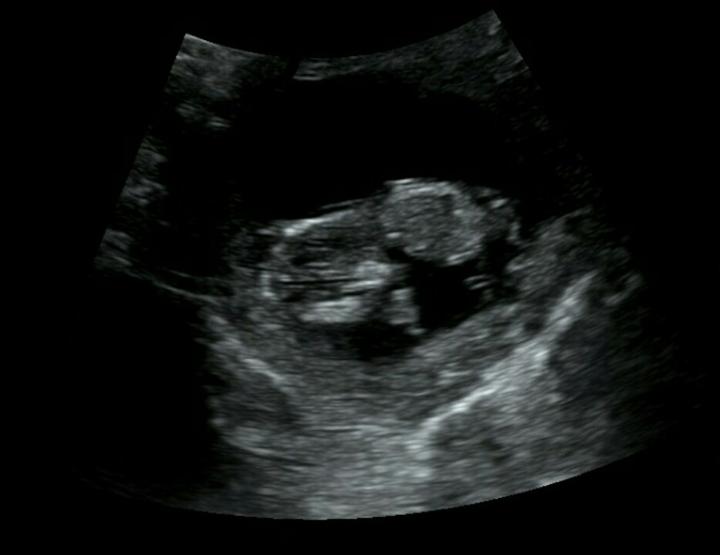

Fotka pořízena v 11+5 tt. 🙂